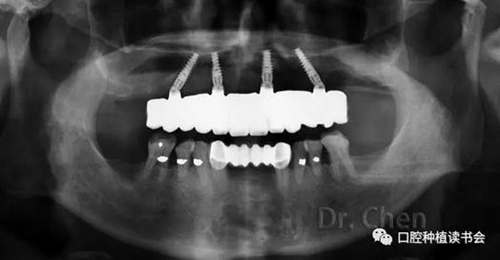

口內(nèi)試戴樹(shù)脂牙,檢查被動(dòng)就位,同時(shí)檢查牙齒形態(tài)、位置、排列,前牙切緣連線與笑線是否協(xié)調(diào)等等,

必要時(shí)用記號(hào)筆標(biāo)注便于技師調(diào)改(圖7),必要時(shí)拍攝曲面斷層片(圖8),可見(jiàn)所有基臺(tái)臨時(shí)套筒完全就位。

8.jpg

▲ 試戴樹(shù)脂牙就位后拍攝曲斷片